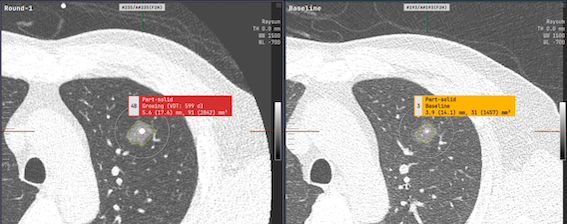

aview LCS automatically detects lung nodules and classifies into 3 types of nodules: solid, non-solid, and GGN from chest CT images. It provides follow-up mode to match the nodules from previous and follow-up exam and calculate volume doubling time to show the changes in volume of the nodule.

• Sensitivity 97%, Specificity 76% at 1-FP/scan

• ROC AUC 0.93

• LungRADS score according to LungRADS 1.1 guideline